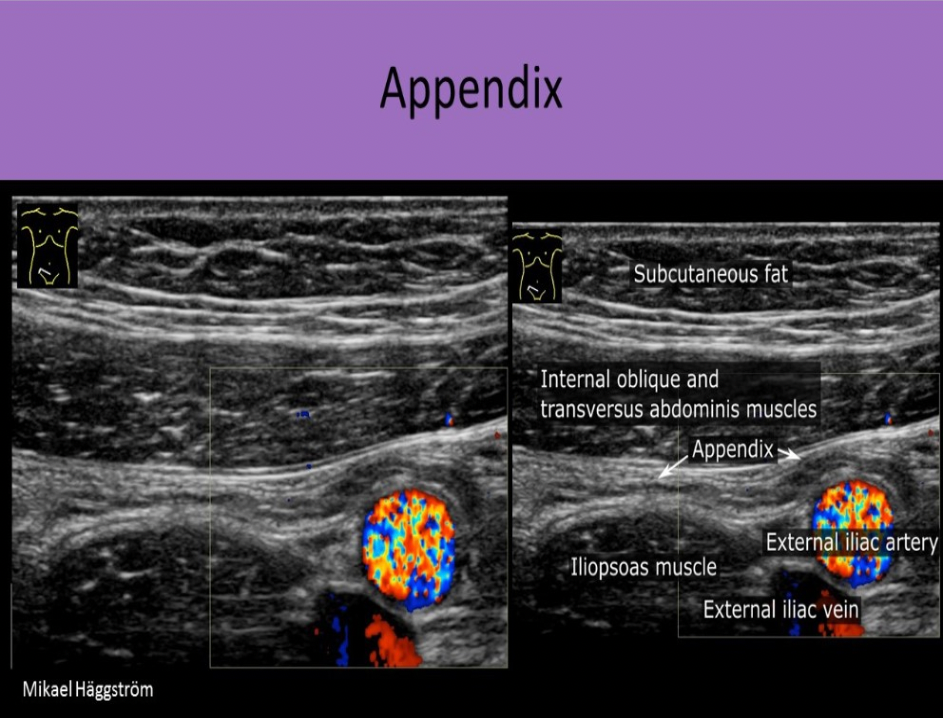

The appendix is normally identified:

A. posterior to the terminal ileum and anterior to the iliac vessels

B. anterior to the terminal ileum and lateral to the iliac vessels

C. originating from the sigmoid colon at the level of the inguinal ligament

D. only in patients less then 150lbs

The appendix is also referred to as the vermiform appendix. It originates from the cecum in most patients and can be identified posterior to the terminal ileum and anterior to the iliac vessels.